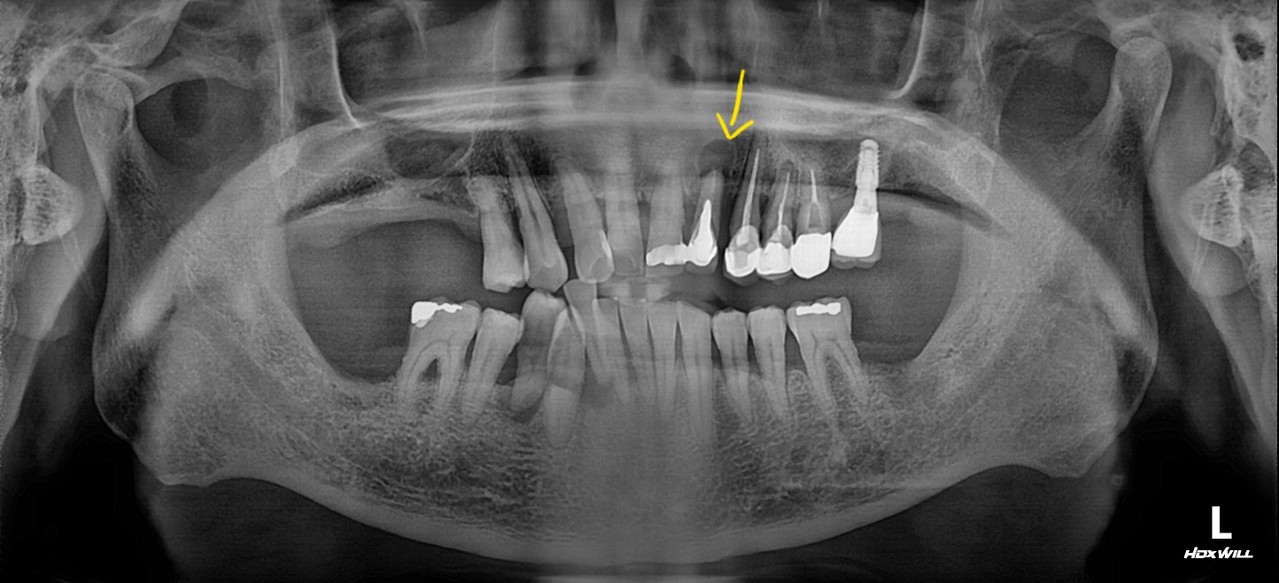

3단계

치수염 (신경까지 감염)

치아 신경까지 세균이 침범하여 심한 통증 발생

신경치료(근관치료) 후 크라운 씌움

본원에서는 올세라믹, 지르코니아 크라운 제작 후 당일 완성 가능

4단계

치근단염 / 낭종 형성

염증이 뿌리 끝까지 퍼짐, 잇몸까지 붓거나 고름 생김

발치 및 임플란트

재신경치료, 외과적 치료 등 필요